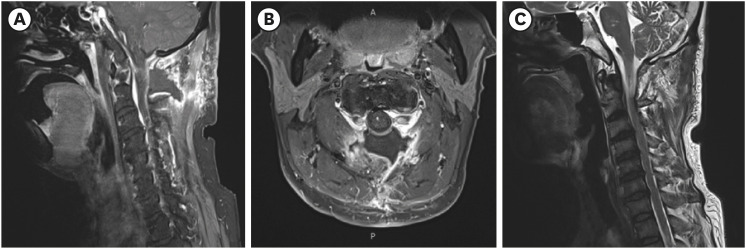

We present a case of cervical myelopathy caused by epidural hematoma formation due to chronic cerebrospinal fluid overdrainage. A 55-year-old man who underwent ventriculoperitoneal (V-P) shunt surgery for normal pressure hydrocephalus presented with progressive weakness of both the upper and lower extremities. Magnetic resonance imaging (MRI) revealed compressive myelopathy at the cervicomedullary junction at the C1-C2 level caused by epidural hematoma formation due to intracranial hypotension (IH) caused by a complication of V-P shunt. He underwent decompressive laminectomy and hematoma removal at C1-C2 and replacement of the V-P shunt valve. Follow-up cervical spine MRI showed an improved state of severe central spinal stenosis at the C1-C2 level and an improved state of compression-related cord signal intensity change in the spinal cord. After surgical intervention and intensive rehabilitation, the patient showed clinical improvement. If cervical myelopathy is suspected in patients with a shunt, cord compression due to venous engorgement or hematoma caused by over-shunting and IH should be considered.

Abstract Image